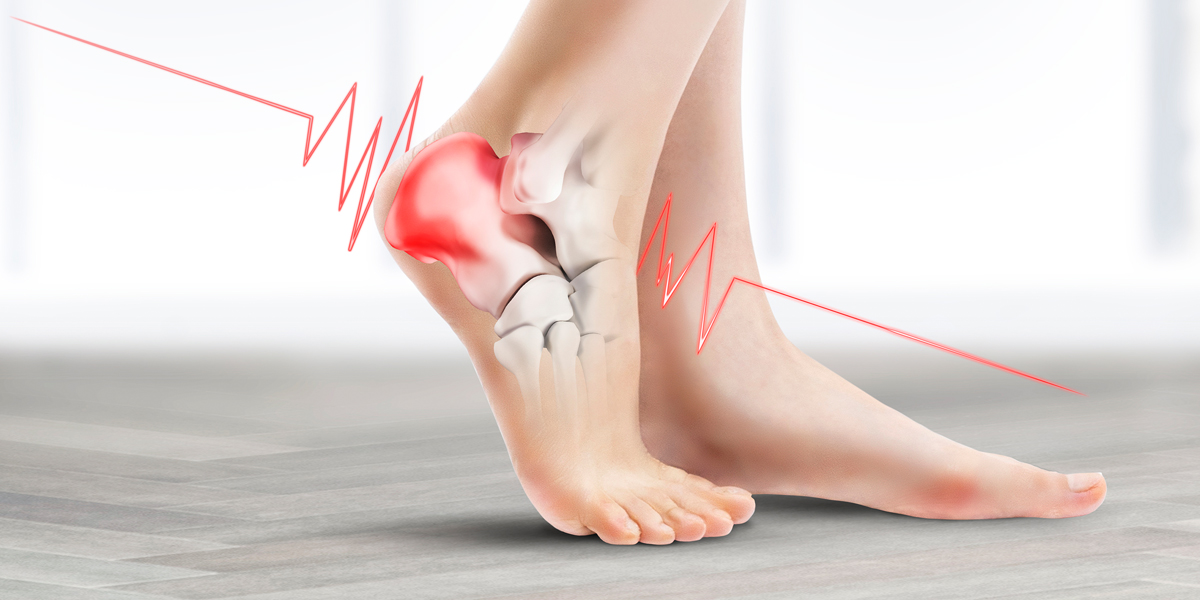

족저 근막염의 가장 대표적인 증상은 발바닥 중앙의 통증입니다. 이 통증은 대개 아침에 일어날 때 가장 심하게 나타나며, 첫 걸음을 내딛을 때 찌릿한 느낌이 들기도 합니다. 통증 정도는 개인에 따라 다를 수 있지만, 대부분 발바닥에 강한 압력이 가해졌을 때 더욱 심해지는 경향이 있습니다.

여섯 번째 증상으로는 발바닥의 조직이 붓는 느낌이 있을 수 있습니다. 통증이 심할 경우, 주변 조직이 부풀어 오르는 것을 느낄 수 있습니다. 이로 인해 더욱 불편한 감각이 발생할 수 있습니다.